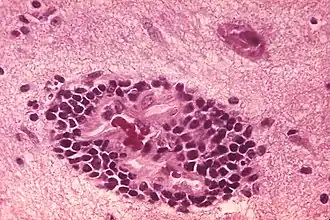

![]() Фотография гистологических изменений, вызванных бешенством | ||||||||